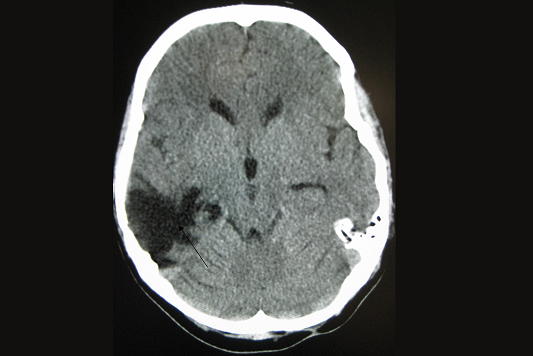

El traumatismo cranoencefálico (TCE) es la afectación del cerebro como consecuencia de la acción de una fuerza externa.